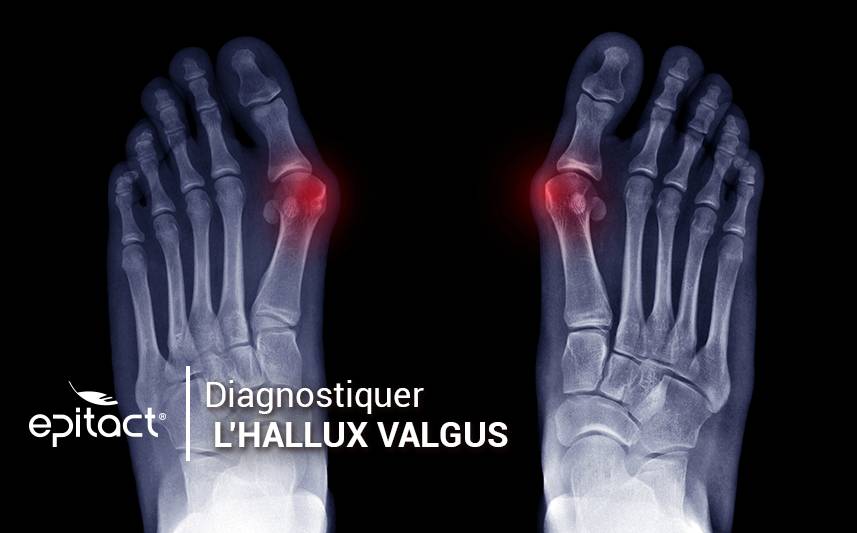

All articles Hallux Valgus